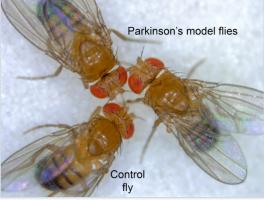

Actualité publiée le 23/02/2017PARKINSON : Cibler les mitochondries pour booster les neurones

PARKINSON : Rétablir les lipides des mitochondries pour bloquer la maladie

PARKINSON : La niacine ou vitamine B3 pour repousser la maladie